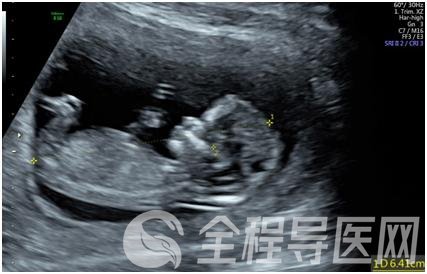

孕早期胎儿超声筛查(NT)已成为评估胎儿生长发育、筛查胎儿畸形的最佳方法,对于防止新生儿出生缺陷、改变妊娠结局,减轻家庭痛苦有着重要的意义,也是排查早孕期胎儿畸形的一项必要检查。

NT检查时间:孕11-13+6周

请务必要在这个时段内完成检查。胎儿头臀长(CRL)一定要在4.5cm-8.4cm之间。

2. 胎儿颈部透明层(NT)

胎儿颈部透明层(NT)是早孕期超声筛查胎儿染色体异常的主要指标。也就是胎儿颈后皮下组织厚度。

NT增厚与唐氏综合征、先天性心脏病的危险性增高有关。